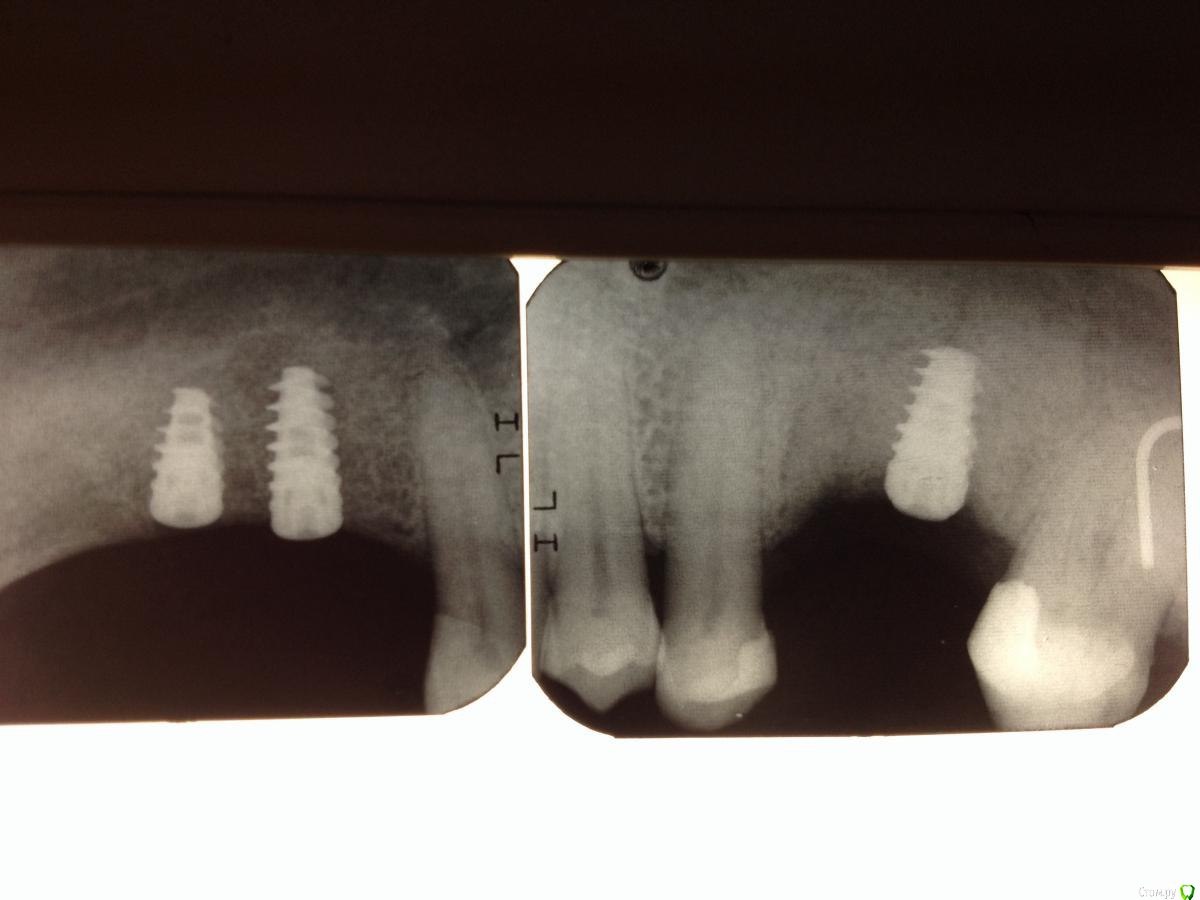

diesel87 Опубликовано 17 октября, 2015 Поделиться Опубликовано 17 октября, 2015 Зачем такой активный имплант на нижней челюсти? Ссылка на комментарий

Shakirbura Опубликовано 17 октября, 2015 Автор Поделиться Опубликовано 17 октября, 2015 Зачем такой активный имплант на нижней челюсти? Плохо? Ссылка на комментарий

diesel87 Опубликовано 17 октября, 2015 Поделиться Опубликовано 17 октября, 2015 Плохо?Это как саморез по дереву вкрутить в кусок бетона или металла. имхо. Подобная форма макрорезьбы и тела больше адаптированы под пористую структуру кости верхней челюсти. Ссылка на комментарий

Shakirbura Опубликовано 17 октября, 2015 Автор Поделиться Опубликовано 17 октября, 2015 Это как саморез по дереву вкрутить в кусок бетона или металла. имхо. Подобная форма макрорезьбы и тела больше адаптированы под пористую структуру кости верхней челюсти.На прогноз это сильно повлияет? Ссылка на комментарий

rivezico Опубликовано 17 октября, 2015 Поделиться Опубликовано 17 октября, 2015 может быть норм , может не очень. не угадаешь Ссылка на комментарий